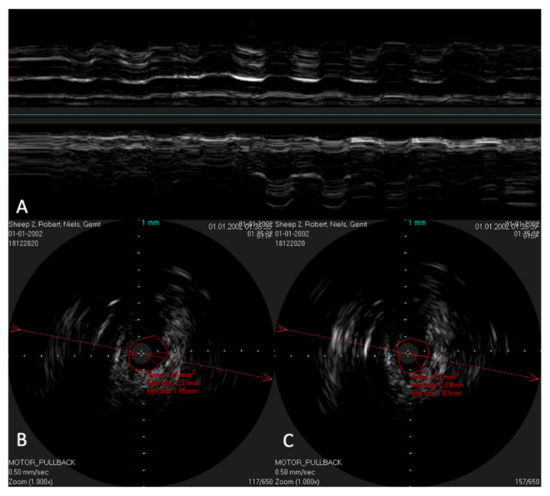

In order to possibly investigate the function of the ET, the lower jaw was moved manually during scans with a stationary IVUS catheter in the ET. An extension of the lumen and, thus, a size change of the lumen could be visualized (Figure 9) in the time-based longitudinal view. With the lower jaw closed, a lumen size of 3.21 mm2 was measured. The probe itself had a size of 1.33 mm2. With the mandible open, this lumen increased to 3.75 mm2. In the longitudinal view, this repetitive size change was clearly visible as waves.

In the in vivo experiments, the IVUS catheter was inserted through the nostrils without any complications. During the insertion of the catheter and the scans, no injuries were detected. The scans were carried out without any problems, both before and after setting an HA depot with 2 mL in the tube course. In a direct comparison of the scans, the depot in the surrounding tissue could also be clearly identified, as shown in Figure 10.

Figure 9. Ultrasound image of the ET with a stationary IVUS probe. During the scan, the lower jaw was repeatedly moved manually, thus opening and closing the sheep’s mouth. Image (A) shows the ET over time. The lumen changes and movements of the surrounding structures can be seen as waves. Part (B) shows the cross-section of the tube with the mouth open, with an approximate tube lumen of 3.75 mm2, where the probe has an area of 1.33 mm2. Part (C) shows the same area with the jaws closed, where the tube lumen has decreased to 3.21 mm2.